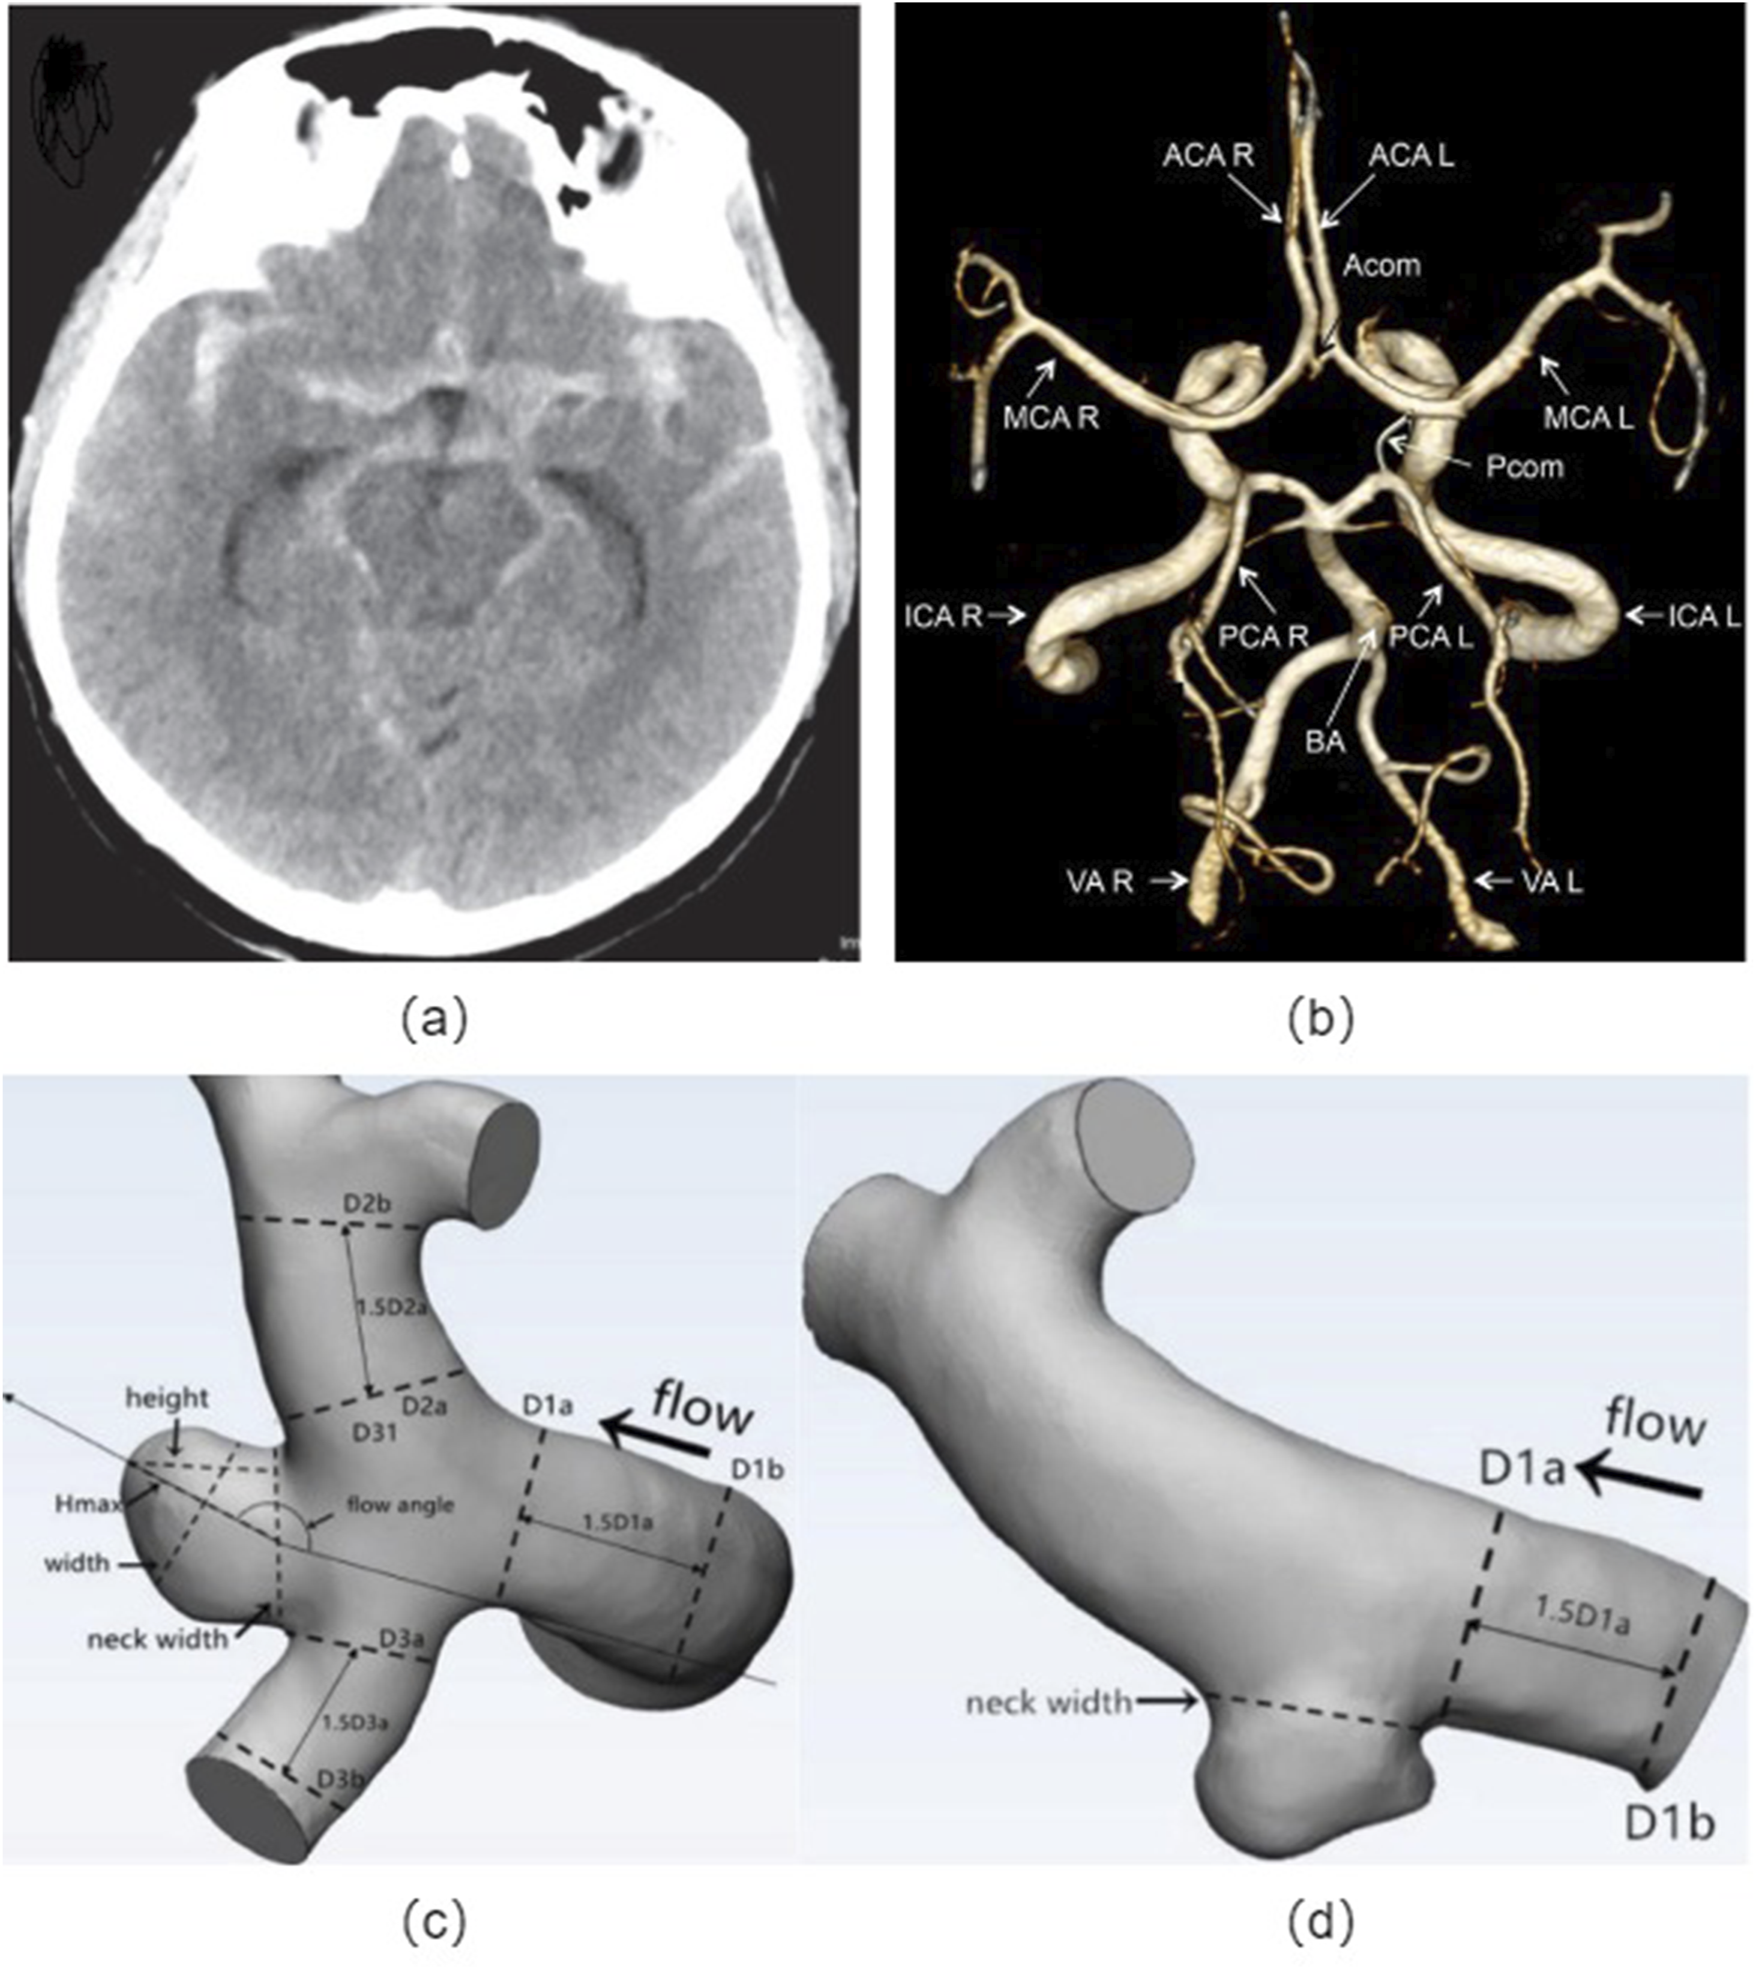

The morphological parameters of cerebral aneurysms mainly include the size, shape, location, and the ratio between various geometrical parameters, which indicates the crucial role in determining the risk of rupture (Kleinloog et al., 2018; Zhu et al., 2020; Baharoglu et al., 2010; Leemans et al., 2019; Liu et al., 2019; Tang et al., 2022). This review aims to provide a comprehensive overview of the relationship between morphological parameters and the risk of rupture in cerebral aneurysms, as shown in Figure 2.

FIGURE 2

Cerebral artery morphology: (A) Non-contrast head CT showing subarachnoid hemorrhage from the left posterior communicating artery aneurysm; (B) Angiographic image of a human circle of Willis, indicated are: vertebral arteries (VA), right (R) and left (L), basilar artery (BA), internal carotid arteries (ICA R, ICA L), posterior cerebral arteries (PCA R, PCA L), anterior cerebral arteries (ACA R, ACA L), middle cerebral arteries (MCA R, MCA L), posterior communicating artery (Pcom) and anterior communicating artery (Acom); Definitions of morphological parameters in the bifurcation aneurysm (C) and sidewall aneurysm (D). Hmax: the maximum distance of the dome from the centroid of the neck plane, Height: the maximum perpendicular distance from the neck plane of the dome, Width: the maximum diameter perpendicular to Hmax, Neck width: the largest cross-sectional diameter of the aneurysm neck plane, aspect ratio (AR) equals to height/neck width, size ratio (SR) equals to Hmax/DV, and DV denote the average of the diameter of the cross-sectional a vessel (Da) just proximal to the neck of the aneurysm and the diameter of the cross-section (Db) at 1.5 times Da from the neck of the aneurysm.